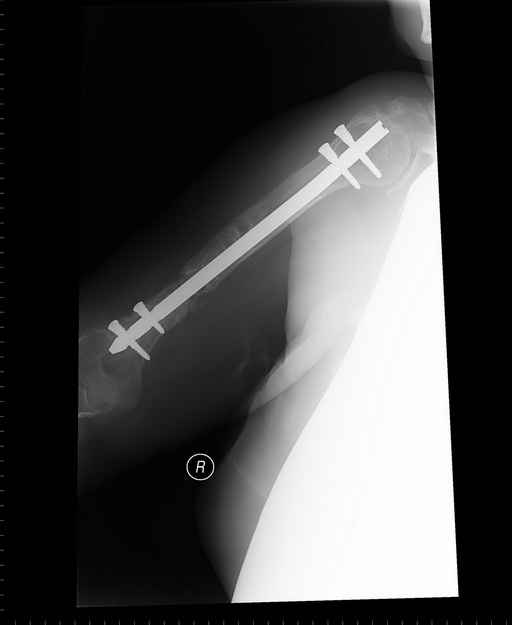

Больная 48 лет, медсестра. Травма получена 7 лет назад, оперирована первично в Турции -

остеосинтез пластиной - несращение - реостеосинтез стержнем там же через год (обычным, с

выстоянеием его в полость плеча) - несращение - поступила к нам впервые в марте 2008 года -

удаление стержня, реостеосинтез пластной и костная пластика, в течение 2 лет лизис кости

вокруг винтов, смещение фиксатора, в марте 2010 - удаление пластины, реостеосинтез

интрамедуллярным стержнем с блокированием (рассверливание + костная пластика).

В динамике - вновь лизис в области перелома, нестабильность дистальных блокирующих винтов.